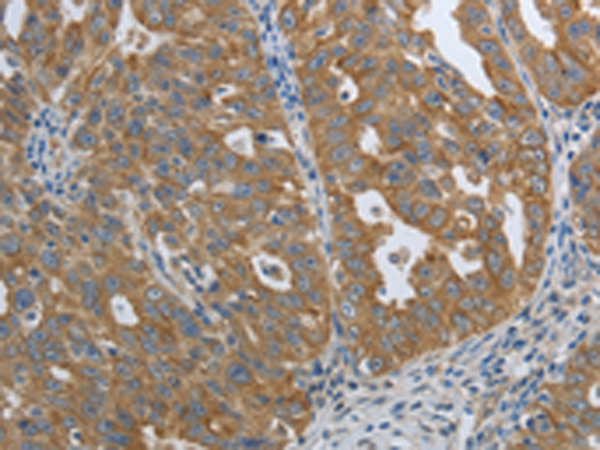

分类: 科研抗体货号: P11313别名: PDGF1, PDGF-A应用: IHC反应种属: Human, Mouse, Rat